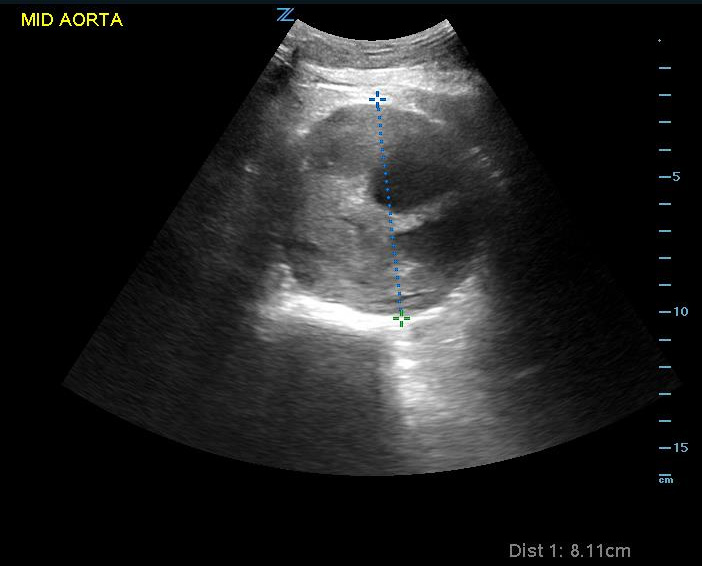

Ultrasound is a valuable modality for determining presence of AAA. This is defined as an aortic diameter > 3cm. Though determination of ruptured AAA is difficult by ultrasound alone, RUSH and similar protocols rely on making a presumptive diagnosis of ruptured AAA as a cause of shock when the aortic diameter measures larger than 5cm while a normal aortic exam would make this diagnosis very unlikely. When performed as part of a rapid evaluation in a hypotensive patient, the most efficient location to visualize is the infrarenal aorta. (Video 16) (Figure 12)

Video 16. Image of abdominal aortic aneurysm in transverse view

Figure 12. Image of abdominal aortic aneurysm measurement. Note luminal thrombus present. Measurement should thus be taken from outside wall to outside wall